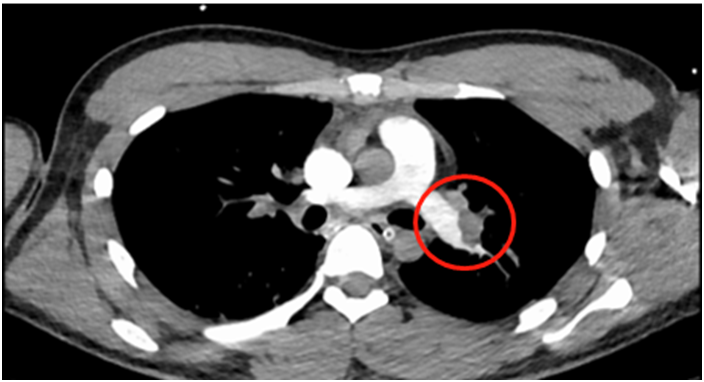

图片

双下肺动脉主干完全闭塞(圆圈所示是堵住肺动脉的血块)